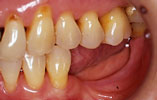

CASE3

下の奥歯2本が欠損 機能的回復

インプラント埋入前

インプラント埋入後

インプラントに

セラミッククラウンを装着

奥歯が2本失われ、従来は取り外し式の部分入れ歯を入れていました。2本のインプラントを埋入し、自分の歯と同様の感覚の「固定式」人工歯を入れ、噛む機能を回復しました。